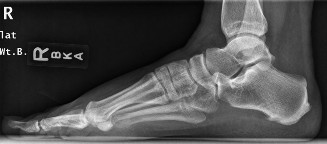

A 48-year-old female presents to your office with worsening right ankle pain. Twenty years ago she sustained …